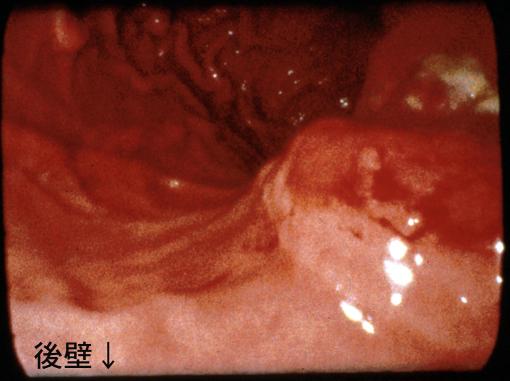

궤양국한형의 위암과 유사한 형태를 나타낸 진행 위 악성 림프종

악성 림프계종양/악성 림프종

위(부위)/체부

2형(궤양국한형)/

40이상

ss(a1)